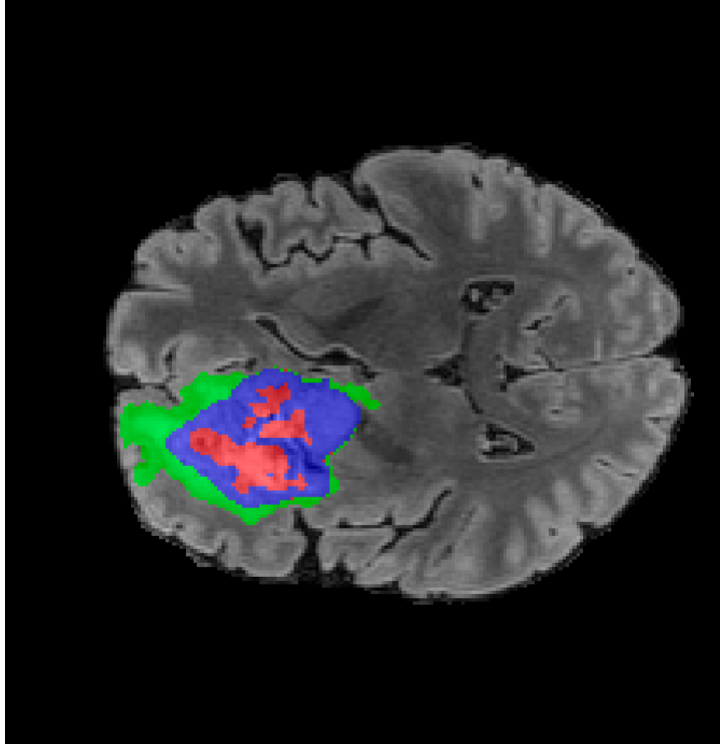

Tumour Information Preservation. For the brain tumor segmentation, we use a Swin UNETR model[27, 70], trained with random rotation, and intensity as data augmentation. In Figure 5, we highlight the tumor profiles of the generated MRIs compared to the ground truth tumour profile. In the test set with human ground-truth annotations (), the real MRI Dice score is 85.15 while the generated MRIs from a single slice have a dice score of 83.09. This shows how the generated MRIs indeed preserve the tumor information and can act as an affordable and informative pseudo-MRI, before conducting an actual costly MRI examination in hospitals.

B.4 Tumour Information Preservation

On the test set with human ground-truth annotations (), the brain volumes generated from single slice input preserve the volume of the different tumour components (paired t-test, for all 3 classes) (see Table 3). The real MRI Dice scores are put for reference to our generated MRIs. X-Diffusion outperforms baselines TPDM [36] and ScoreMRI [18] in tumour preservation (see Table 3 and Figure 12). We ran experiments comparing the tumour segmentation Dice Score varying X-Diffusion configurations. The multi-slice input X-Diffusion achieves a marginally better Dice Score than the single-slice input model (83.47 83.09). We also ran experiments with slice input used for volume reconstruction intersecting or not with tumour. We observe on average a drop of 6% Dice Score (see Table 3). Further away from the tumour the input slice for volume reconstruction is selected, and we observe a linear decrease in tumour segmentation Dice Score with the lowest value of 77.21 Dice Score (see Figure 15).